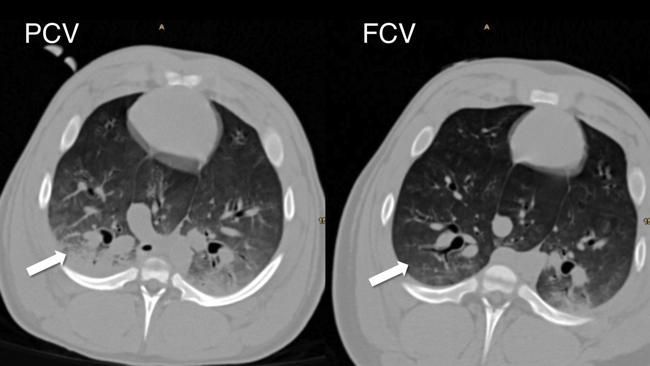

Our group investigates flow-controlled ventilation (FCV) as a novel ventilation method established to guarantee a continuous, constant and typically identical flow during inspiration and expiration. Additionally, the constant flow coupled with direct intratracheal pressure measurement allows accurate evaluation of dynamic compliance and adjustment of ventilation settings accordingly. Our first experimental pilot study demonstrated more efficient gas exchange and improved oxygenation as well as less atelectasis in individualised FCV compared with pressure-controlled ventilation (PCV) at the best standard of care during long term ventilation. Similar results were observed in an experimental model of single lung ventilation and in an experimental model of acute respiratory distress syndrome. Two clinical ventilation studies are currently being conducted in patients undergoing cardiac surgery and thoracic surgery with single lung ventilation, comparing individualised FCV with standard-of-care PCV.

• Spraider, P.; Martini, J.; Abram, J.; Putzer, G.; Glodny, B.; Hell, T.; Barnes, T.; Enk, D.: Individualized flow-controlled ventilation compared to best clinical practice pressure-controlled ventilation: a prospective randomized porcine study. CRITICAL CARE. 2020; 24(1): 662.

• Enk, D.; Spraider, P.; Abram, J.; Barnes, T.: Pressure Measurements in Flow-Controlled Ventilation. CIRTICAL CARE MEDICINE. 2020; 48(12): e1359-e1360.